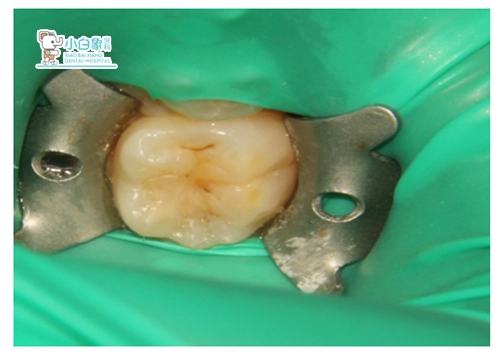

治疗过程:表麻膏涂布游离龈及牙龈乳头后,上橡皮樟,去腐质,备洞隔湿干燥,行Z350充填,调合,抛光。

QQ截图20181220150512